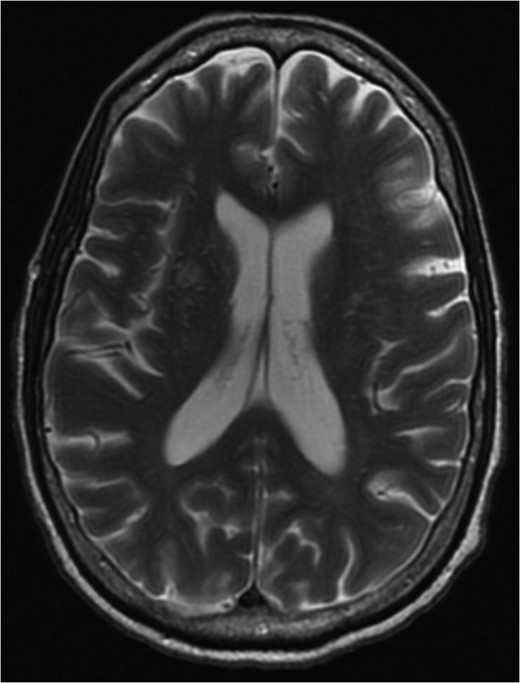

MRI brain 3 months post-diagnosis, Axial T2 sequence. Normalization of imaging with resolution of vasogenic edema and pneumocephalus.